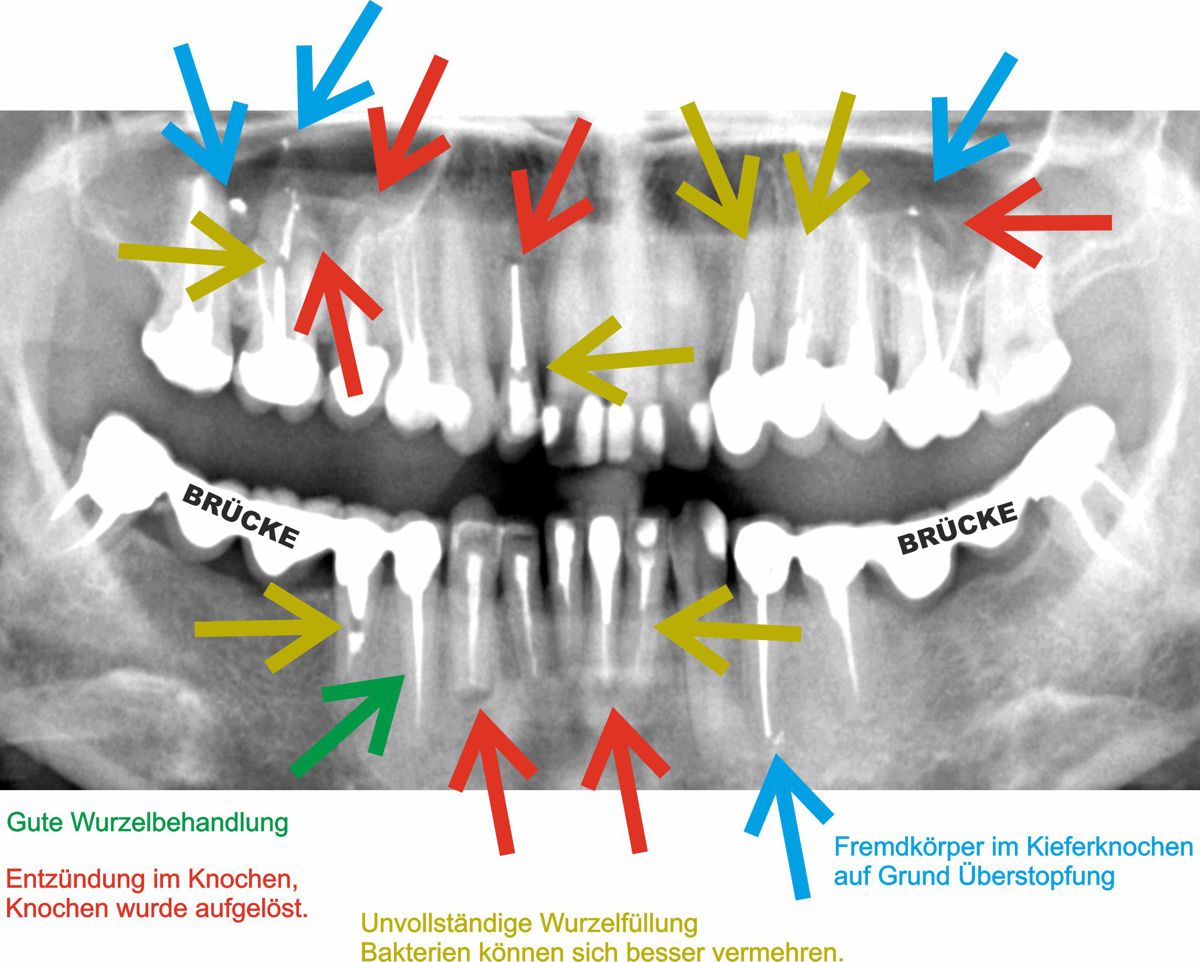

Hier sind die Zähne vollständig zu sehen, im Gegensatz zu den sog. Bite Wings, wo es nur darum geht, zu erkennen, ob Karies an den Zahnhälsen vorliegt.

Dies im Gegensatz zu diesem Patienten:

Es liegen hier viele wurzelbehandelte Zähne vor, welche zudem schlecht gemacht wurden, und entsprechend viele Hinweise auf gesundheitlich belastende Zustände.

Schlechte Wurzelbehandlungen sind auch erkennbar an den unregelmässigen Rändern welche die meisten der wurzelbehandelten Zähnen aufweisen (vergleichen Sie mit dem grünen guten wurzelbehandelten Zahn.).

Sollte so jemanden sich über chronische Entzündungen beschweren, so ist es Pflicht von jedem Arzt und Zahnarzt, solche potentielle Herde in den Überlegungen mit einzubeziehen.